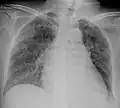

| Chest X ray showing miliary tuberculosis | |

Miliary tuberculosis is a form of tuberculosis that is characterized by a wide dissemination into the human body and by the tiny size of the lesions (1–5 mm). Its name comes from a distinctive pattern seen on a chest radiograph of many tiny spots distributed throughout the lung fields with the appearance similar to millet seeds—thus the term "miliary" tuberculosis. Miliary TB may infect any number of organs, including the lungs, liver, and spleen.[2]